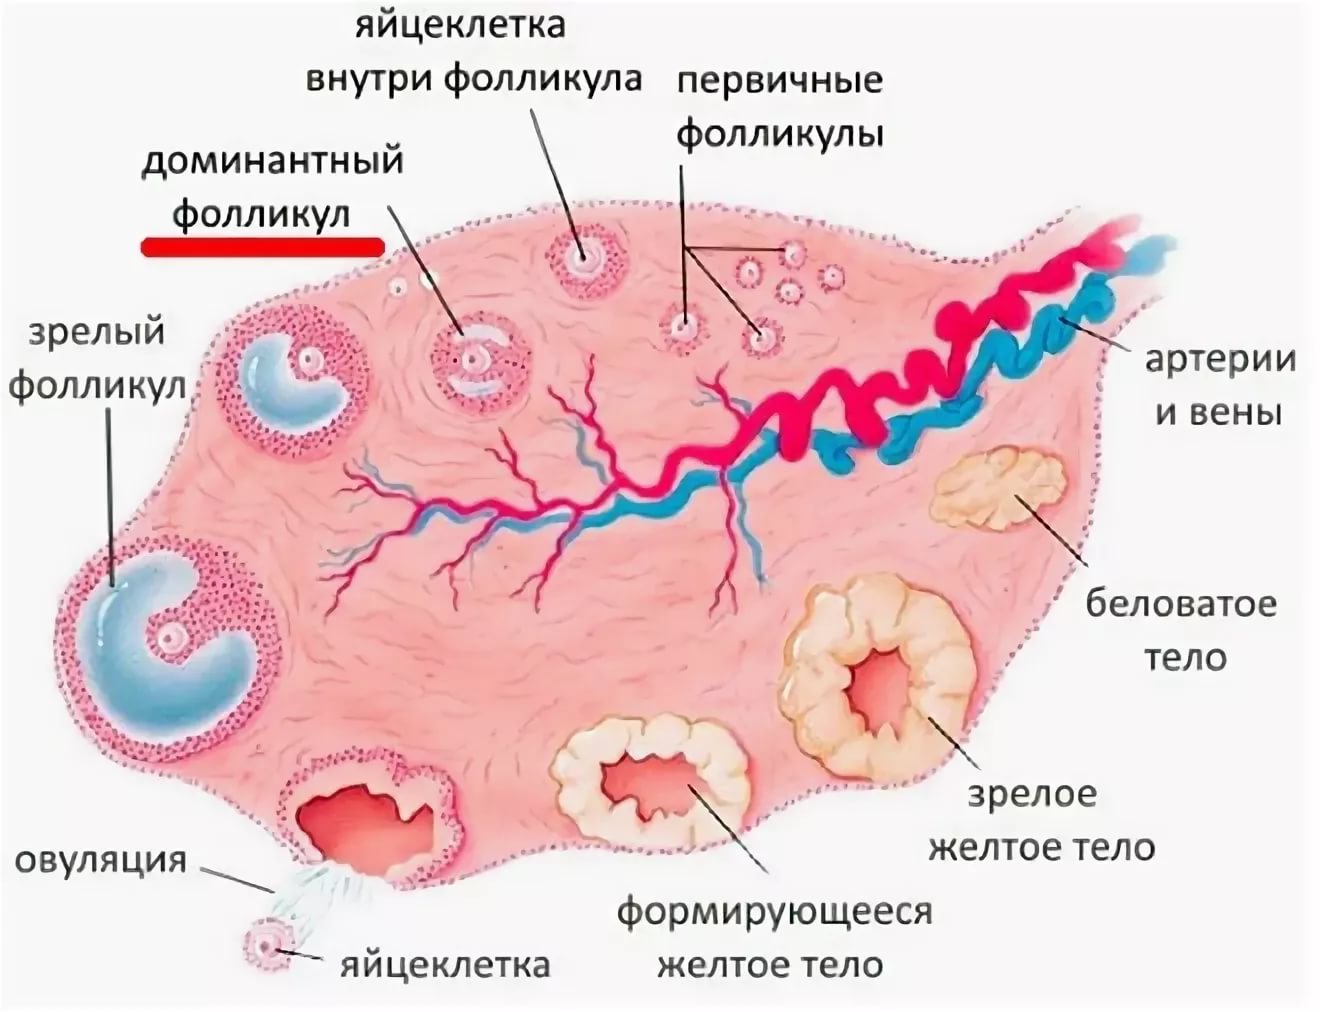

Созревание фолликула в яичнике: этапы и процессы